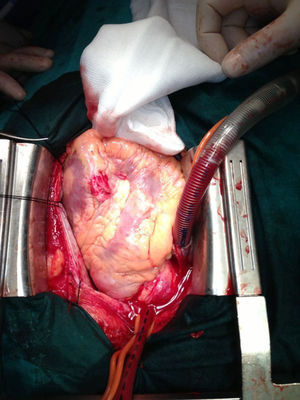

Se demostró un coágulo de gran tamaño (fig. 2)2 que comprimió localmente la hemorragia aunque derivó insidiosamente al taponamiento tardío. Tres lesiones inciso-punzantes en ventrículo derecho, una de ellas sobre el territorio de la descendente anterior con afectación distal de la misma y sangrado insidioso pulsátil activo que derivó al carácter tardío de la clínica.

Se desestimó la revascularización por su localización distal y se realizó sutura directa apoyada en pericardio y parche adherido con cianoacrilato con oclusión de la misma (figs. 3 y 4).